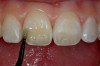

Figure 8  Completed direct composite restorations on tooth Nos. 8 and 9.

Figure 8